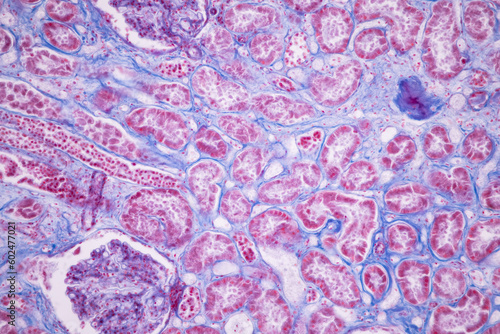

Mikrofotografi - Plakater, Poster, Billeder på lærred